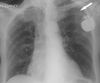

The cause of the patient's pacemaker malfunction was demonstrated by a chest radiograph, which revealed a fracture in the pacing wire (Figure 2). This wire fracture caused not only the failure to capture but also a failure to sense native ventricular activity-and even some degree of failure to pace. Note the low amplitude pacer spikes, which indicate low-voltage transmission to the myocardium.